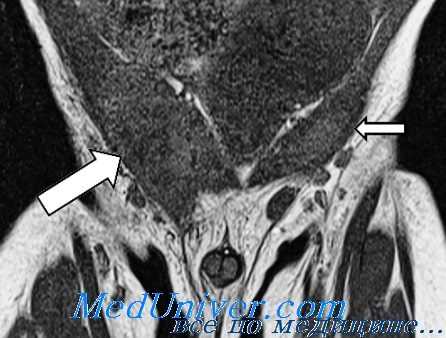

3. МРТ при неопущении яичка:

• Визуализация посредством МРТ должна применяться в УЗ-негативных случаях

• Т1-ВИ: объемное образование овальной формы с низкой интенсивностью сигнала; Т2-ВИ: объемное образование овальной формы с высокой интенсивностью сигнала

(Слева) На рисунке показано яичко, расположенное в верхней части мошонки вследствие его неполного опущения. Неопущенное яичко может быть локализовано в любом месте в проме жутке между почкой и паховым каналом.